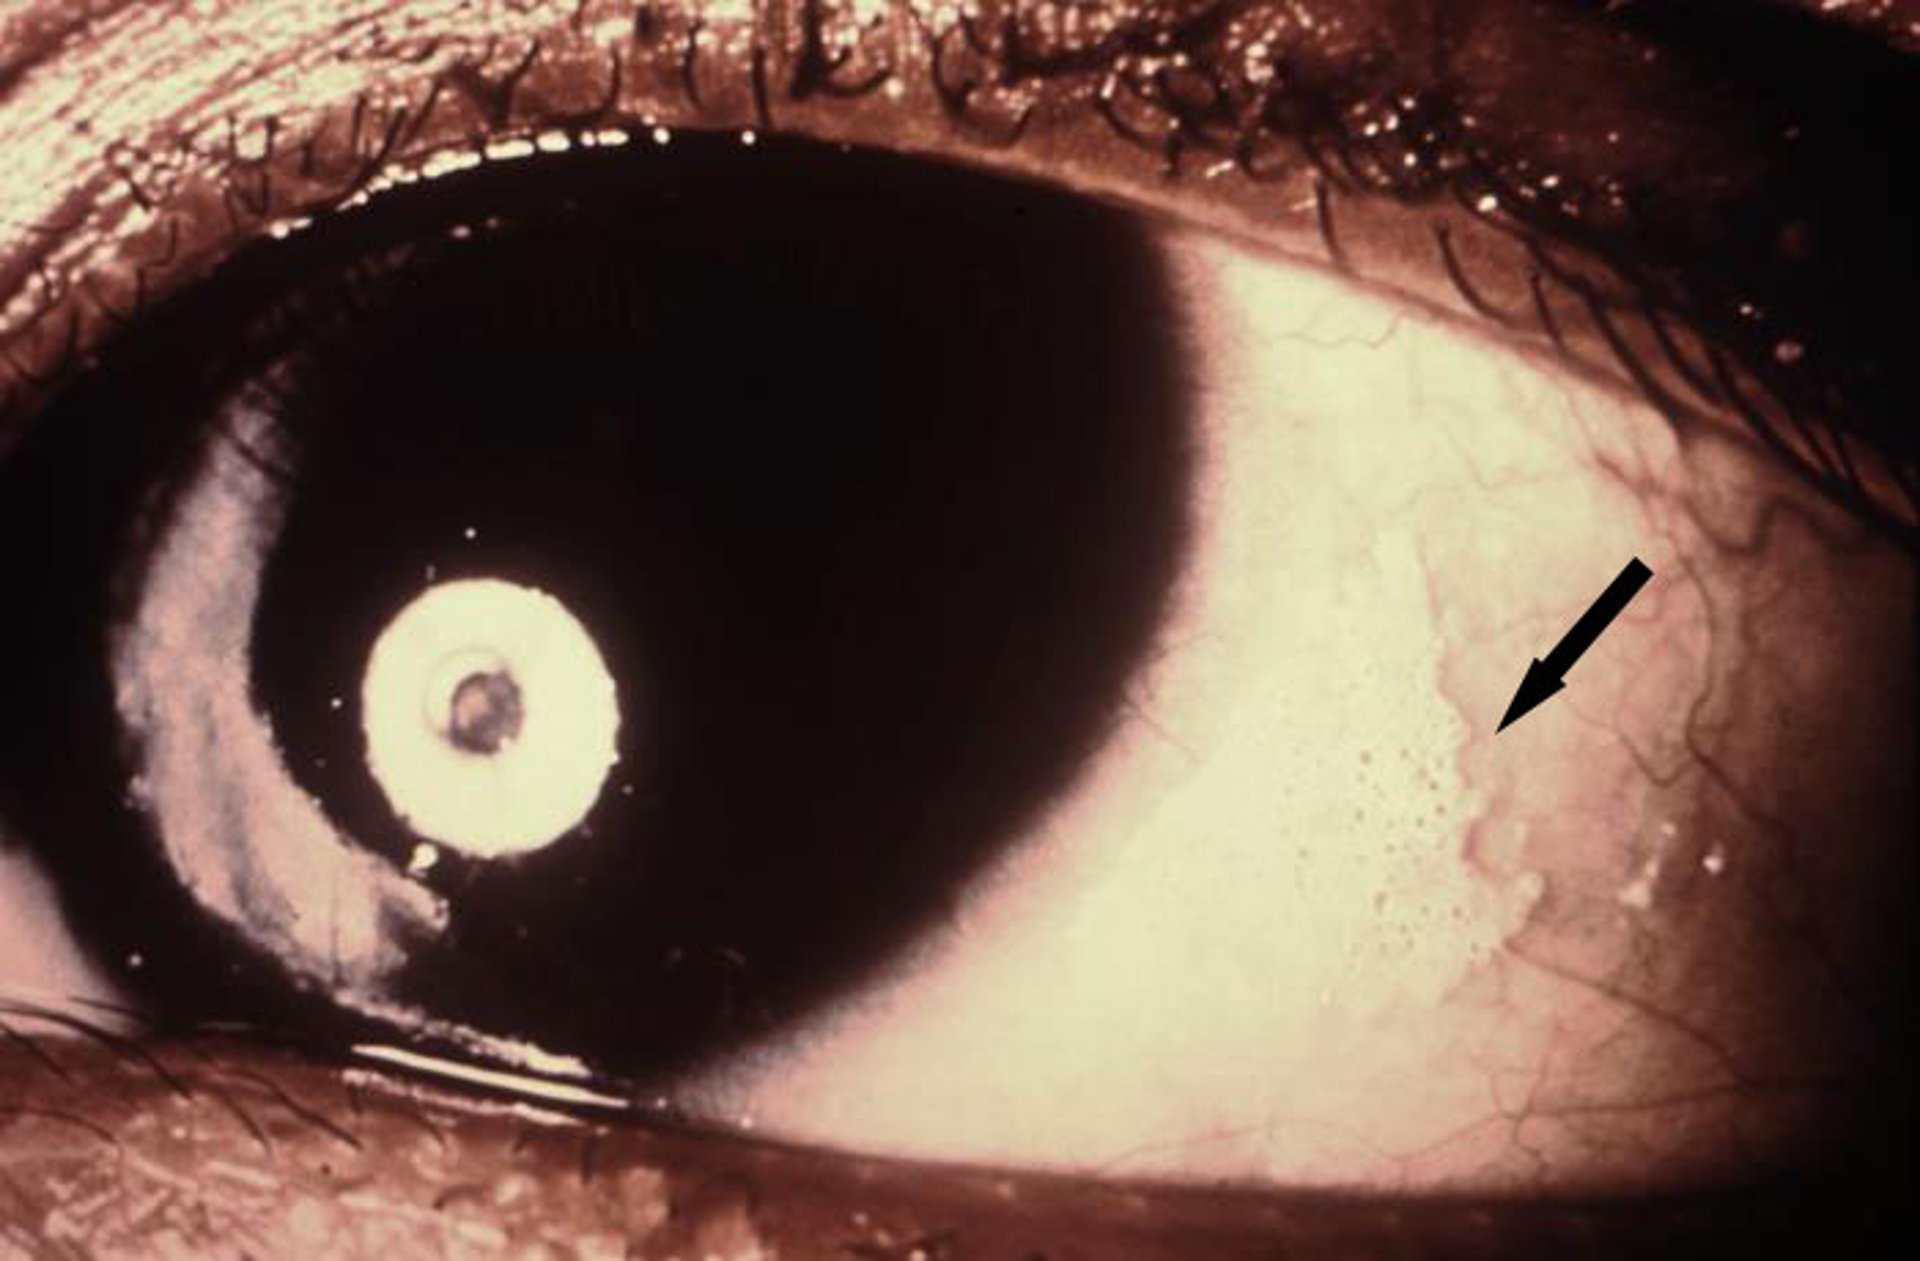

Xeroftalmia

Esta foto mostra secura crônica da membrana conjuntival com manchas queratinizadas conhecidas como manchas de Bitot (seta).